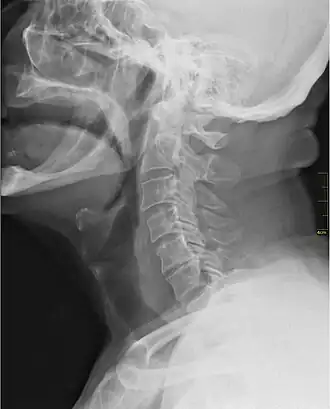

![]() Rayos X mostrando la garganta. | ||